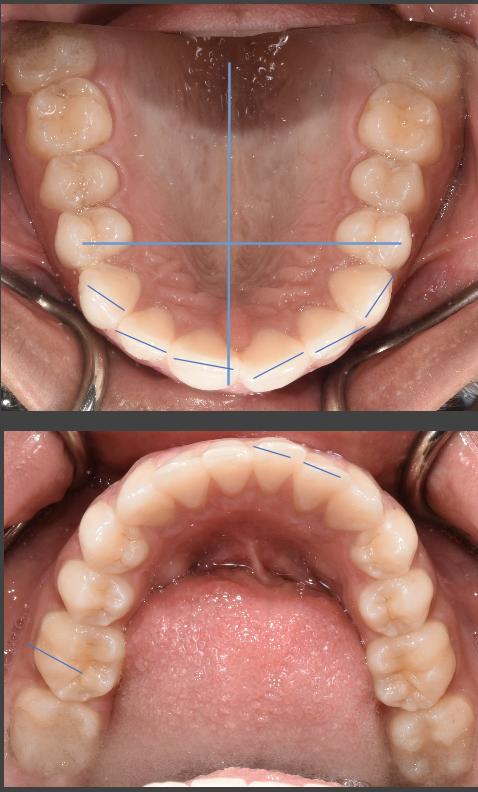

Almost-brodie bite with SFOT. Looking for provider recommendations

I went to my original orthodontist really wanting a wider smile and a fix to my overbite {content removed} sleep apnea. He proposed removing two premolars in order to prepare for double jaw surgery. I had the two lower premolars removed in addition...